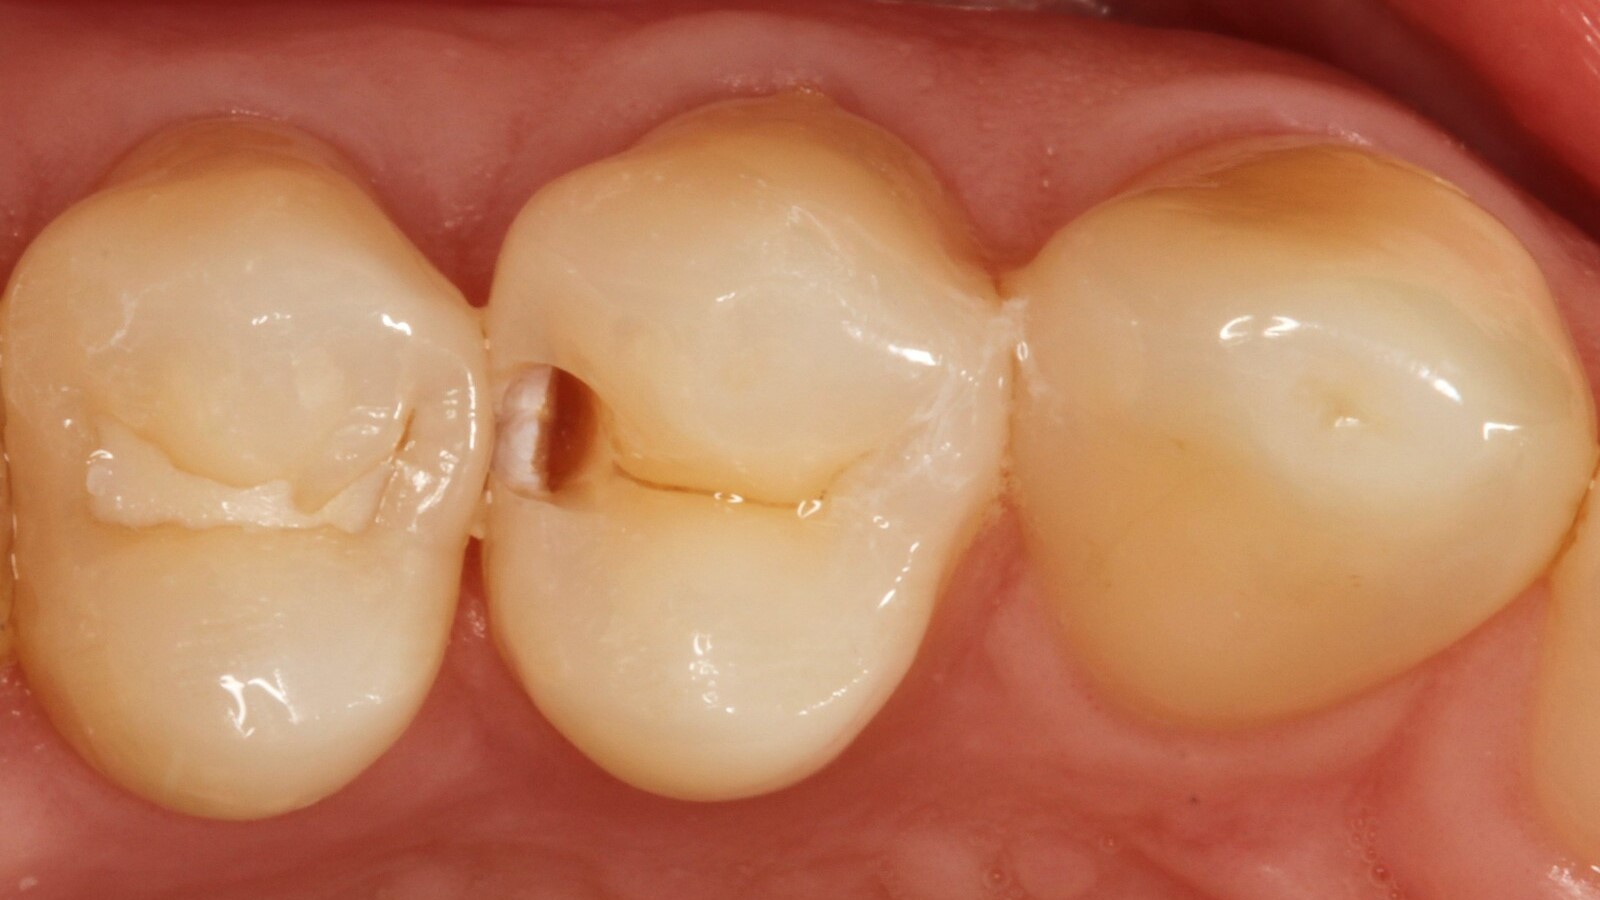

Le professeur Ernst a d'abord identifié les caries non visibles et a ouvert la lésion carieuse pour montrer le problème au patient (Fig. 1-2). Il a ensuite excavé la carie, préparé la cavité et placé une matrice sectionnelle (Fig. 3) avant de sceller la cavité avec de l'adhésif (Fig. 4). En une seule étape, il a rempli la cavité avec Venus Bulk Flow ONE (Fig. 5). Une fois la restauration terminée, le Pr Ernst l'a polie (Fig. 6) et a pris une radiographie de contrôle, qui montre également l'excellente radiopacité de Venus Bulk Flow ONE (Fig. 7).